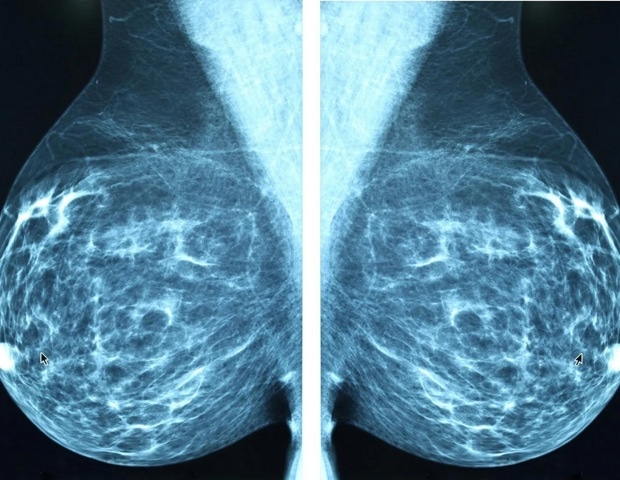

ТНРМЖ широко признан как рак молочной железы, который наиболее трудно поддается лечению, поскольку он очень агрессивен и не реагирует на таргетную терапию, такую ??как иммунотерапия или гормональная терапия, которые могут использоваться при других подтипах. Из-за отсутствия таргетной терапии у пациентов с ТНРМЖ прогноз часто плохой. Чтобы восполнить этот пробел в доступных методах лечения, исследователи рака работают над поиском новых способов борьбы с этим неуловимым раком, например, путем воздействия на молекулярные механизмы, которые раковые клетки используют, чтобы оставаться в живых.